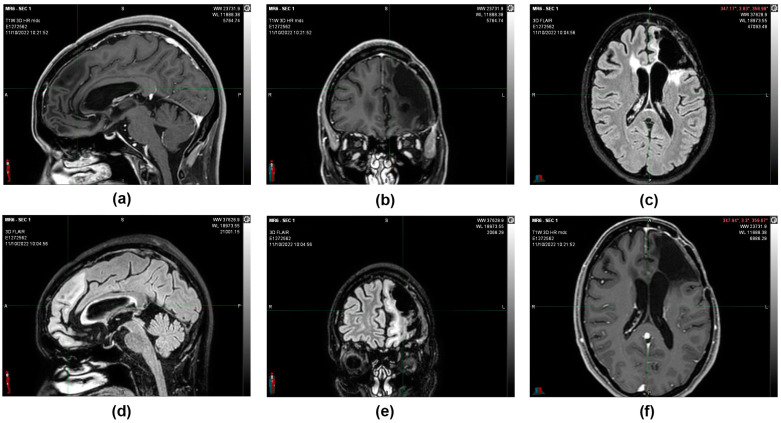

During the follow-up, quarterly visits, clinical-instrumental checks, and monthly blood and biochemistry tests were carried out. At the end of the first cycle of O2O3 therapy (9 February 2017), the 2 cm residual tumor mass that was present 3 months before was no longer visible on the brain magnetic resonance imaging (MRI) (Figure 3), and the stable-negative tumor mass was confirmed with the MRI on 11 October 2022 (Figure 4).

MRIs were done in subsequent periods (12 July 2021 and 11 October 2022), confirming that the morphological picture remained stable and that the patient was considered cured (Figure 5).